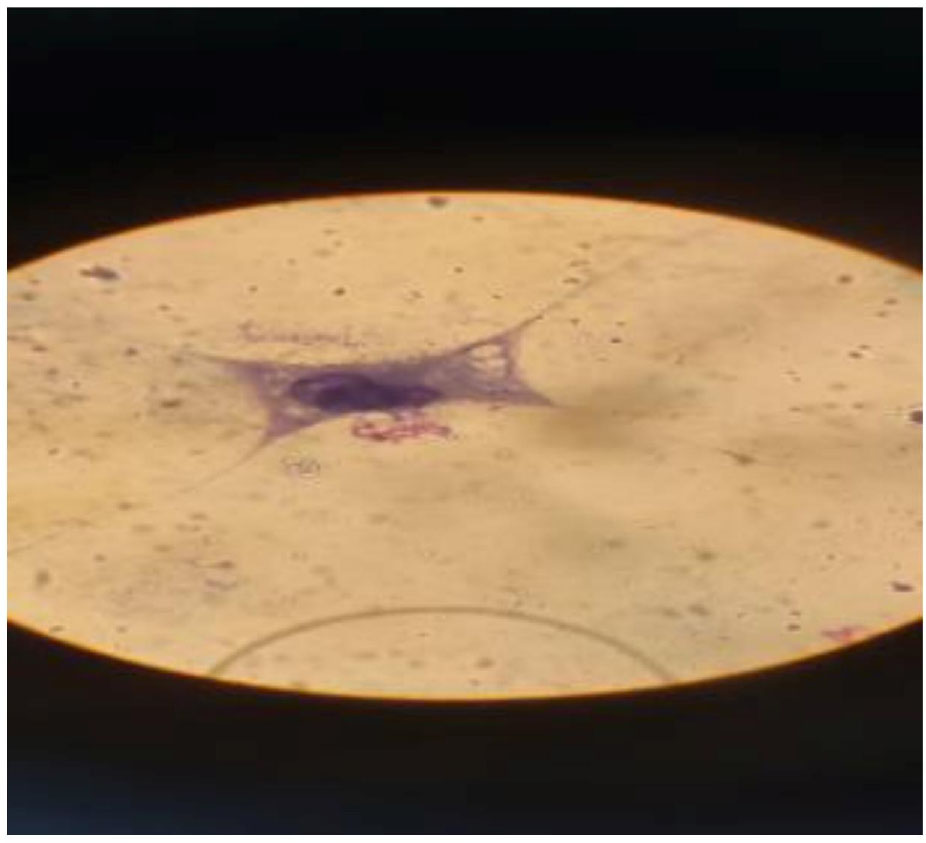

3.1.4. Infected Cells and Number of Tachyzoite in HeLa Cells

The results from cell culture showed that at higher concentrations of linezolid, the number of tachyzoites decreased (Fig. 6). In addition, HeLa cells were viable in the culture media, which could be seen under the microscope (Fig. 6). The percentage of parasite-infected cells 24 h after drug exposure compared to the control groups is demonstrated in Fig. (7). Additionally, the mean and standard deviation of tachyzoite counts in treated and control cells after 24 h are illustrated in Fig. (8).

Infected and intact cells in HeLa cells in cell culture by microscope 100X.